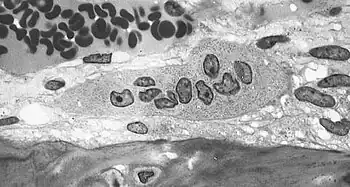

| Light micrograph of an osteoclast displaying typical distinguishing characteristics: a large cell with multiple nuclei and a "foamy" cytosol. | |

The osteoclasts are multi-nucleated cells that contain numerous mitochondria and lysosomes. These are the cells responsible for the resorption of bone. Osteoblasts are generally present on the outer layer of bone, just beneath the periosteum. Attachment of the osteoclast to the osteon begins the process. The osteoclast then induces an infolding of its cell membrane and secretes collagenase and other enzymes important in the resorption process. High levels of calcium, magnesium, phosphate and products of collagen will be released into the extracellular fluid as the osteoclasts tunnel into the mineralized bone. Osteoclasts are prominent in the tissue destruction found in psoriatic arthritis and rheumatological disorders.[3]